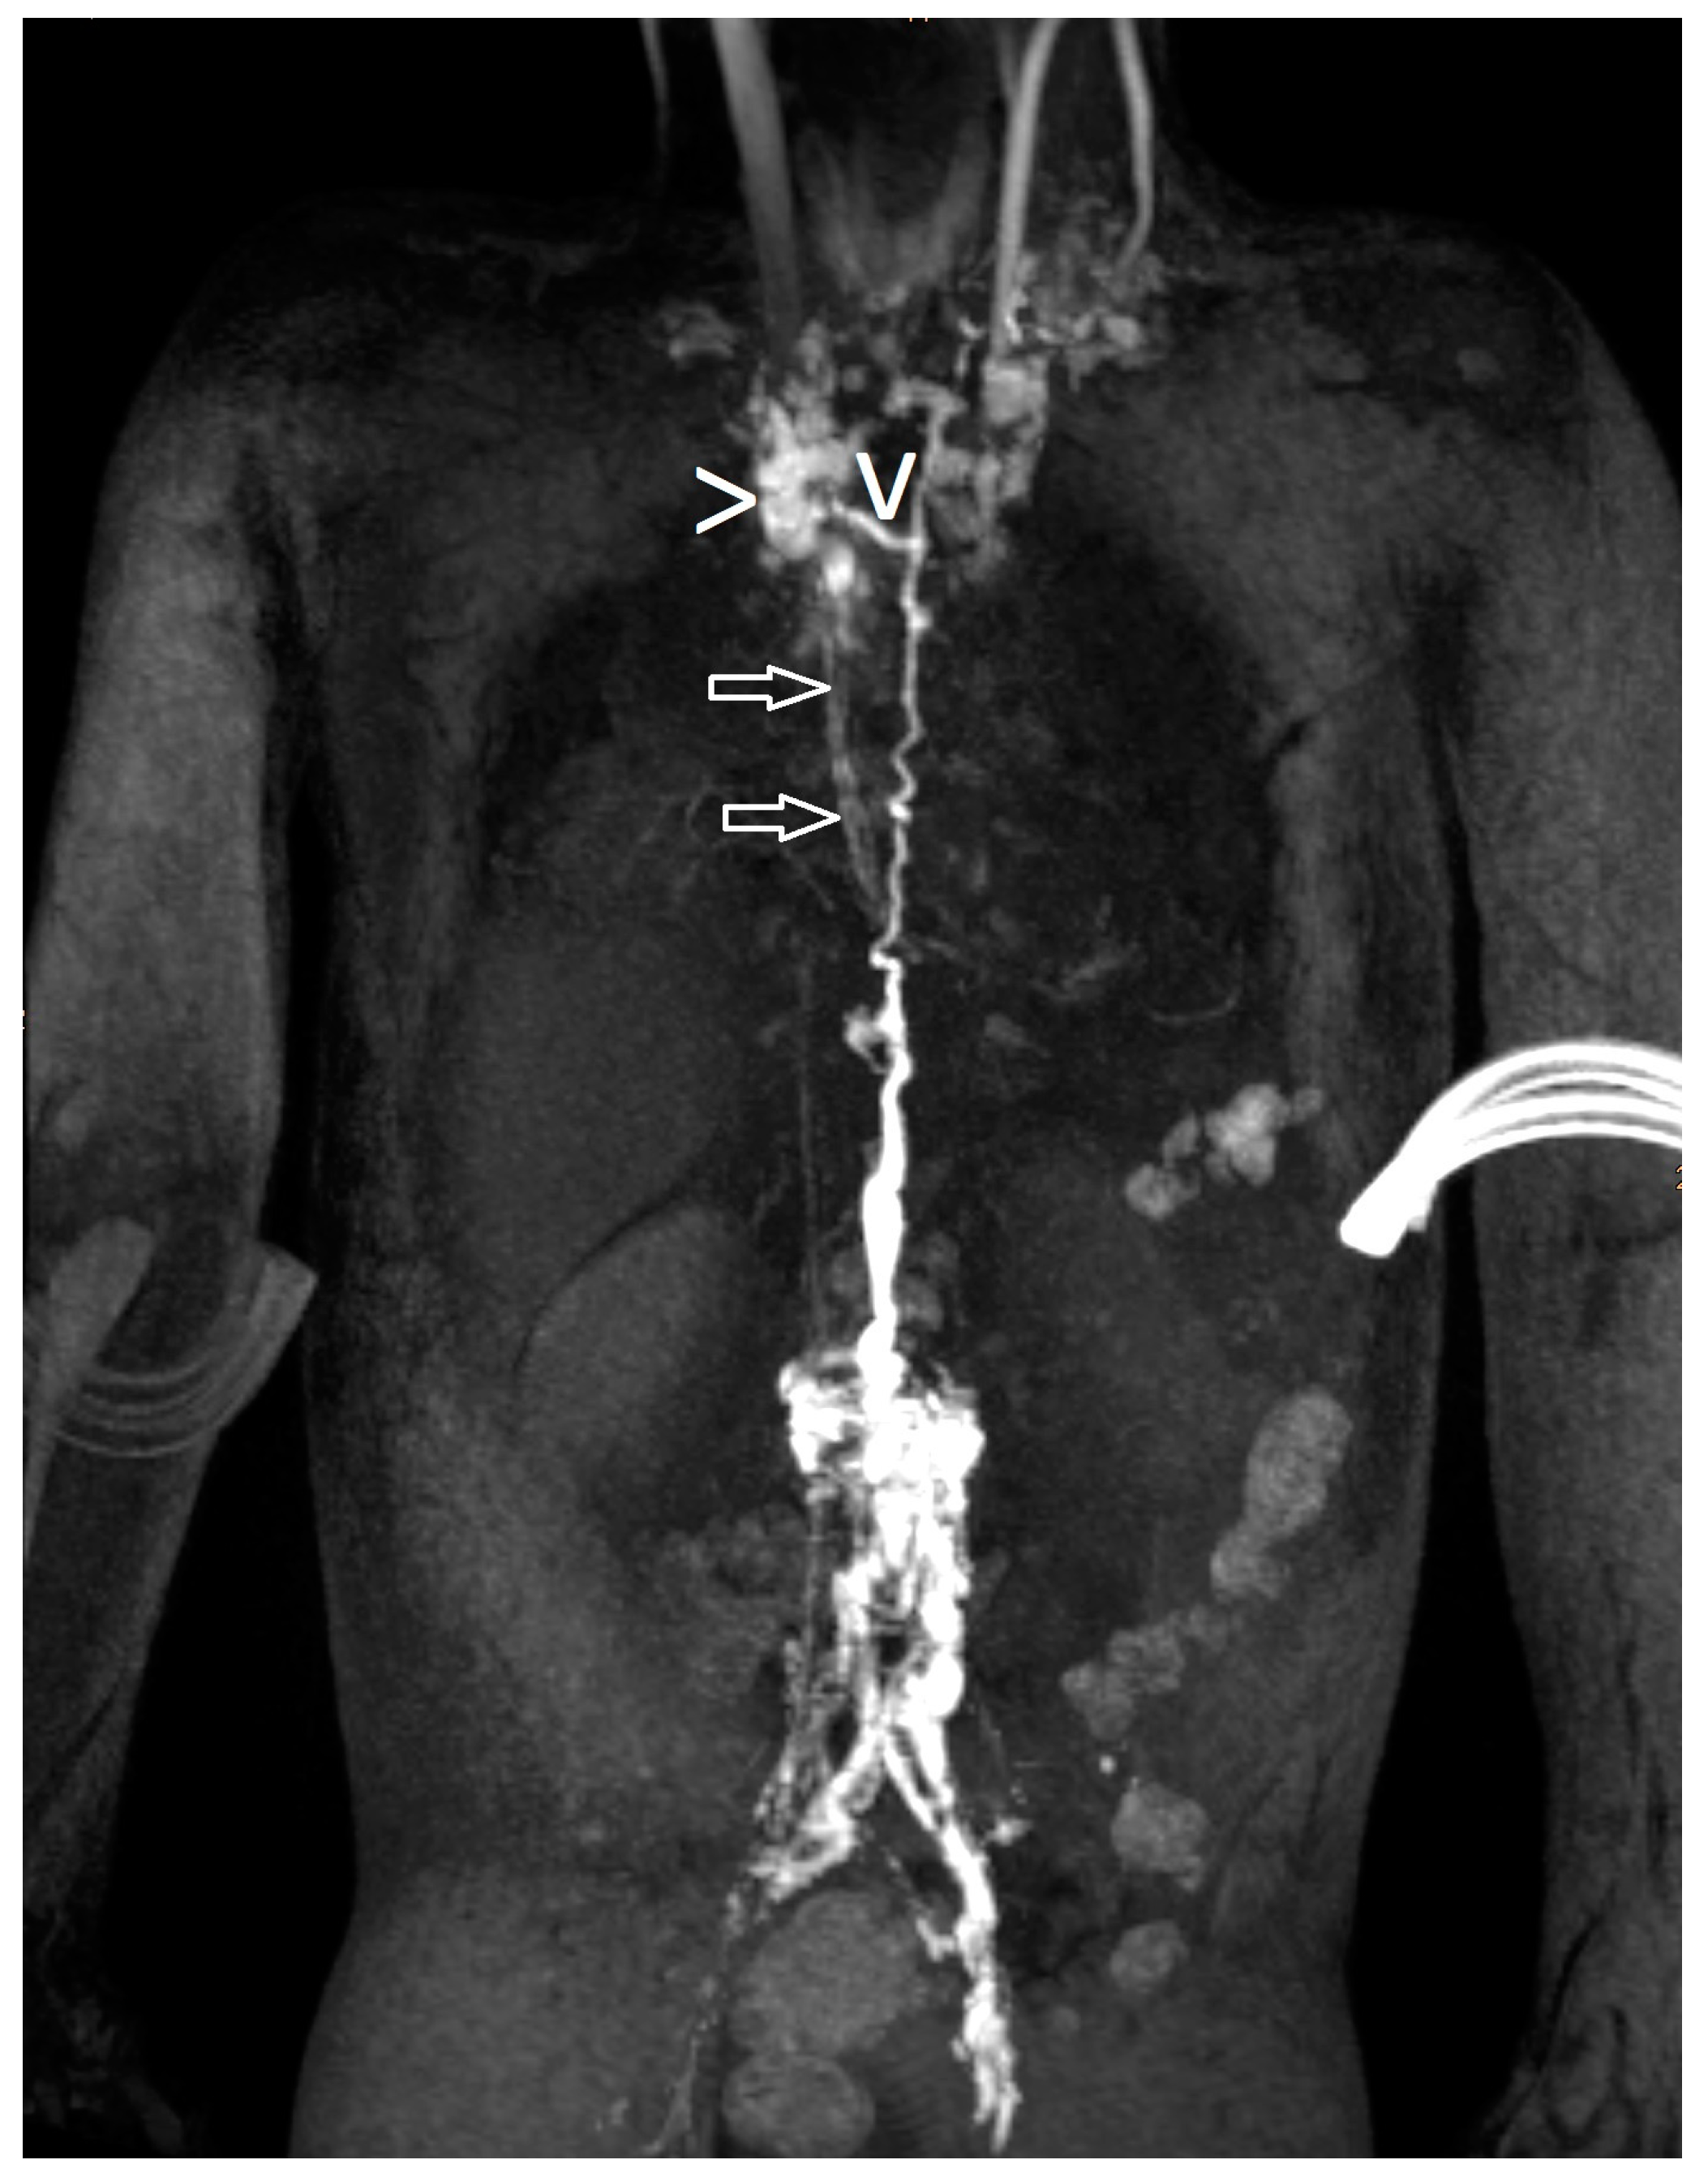

| 21 | 4 | increased signal mediastinum, hilum, lung le > ri | retrograde flow from TD with diffuse mediastinal and peribronchial perfusion | thoracic vertebrae 4–10 to left mediastinum | MCT diet, macitentan, alteplase inhalation, salbutamol, diuretics | glue embolization of TD | cast free after intervention (FU 1 a 4 m) tapering off sildenafil |

| 22 | 4 | increased signal (mediastinum), hilum/lung ri | retrograde lymphatic flow to mediastinum and lung parenchyma ri | from hilum to ri lung | fat reduced diet, sildenafil, alteplase/ fluticasone inhalation | selective glue embolization of 2 branches of TD | cast free after intervention (FU 4 a), cessation of fat-reduced diet, |

| 23 | 4 | increased signal mediastinum, hilum, lung ri > le | retrograde lymphatic flow towards lung parenchyma & mediastinum ri > le and peribronchial perfusion | fistula visualized | fat reduced diet, sildenafil, diuretics, alteplase inhalation, azithromycine | selective glue embolization of fistulas | cast free after intervention (FU 1 a 4 m) |

| 24 | 4 | increased signal at the mediastinum and hilum bilateral | retrograde lymphatic flow towards mediastinum and hilum bilaterally | no fistula visualized | diuretics salbutamol inhalation. Budesonide | TD decompression | cast free after OP, albumin normalized (FU 3 a 5 m) |